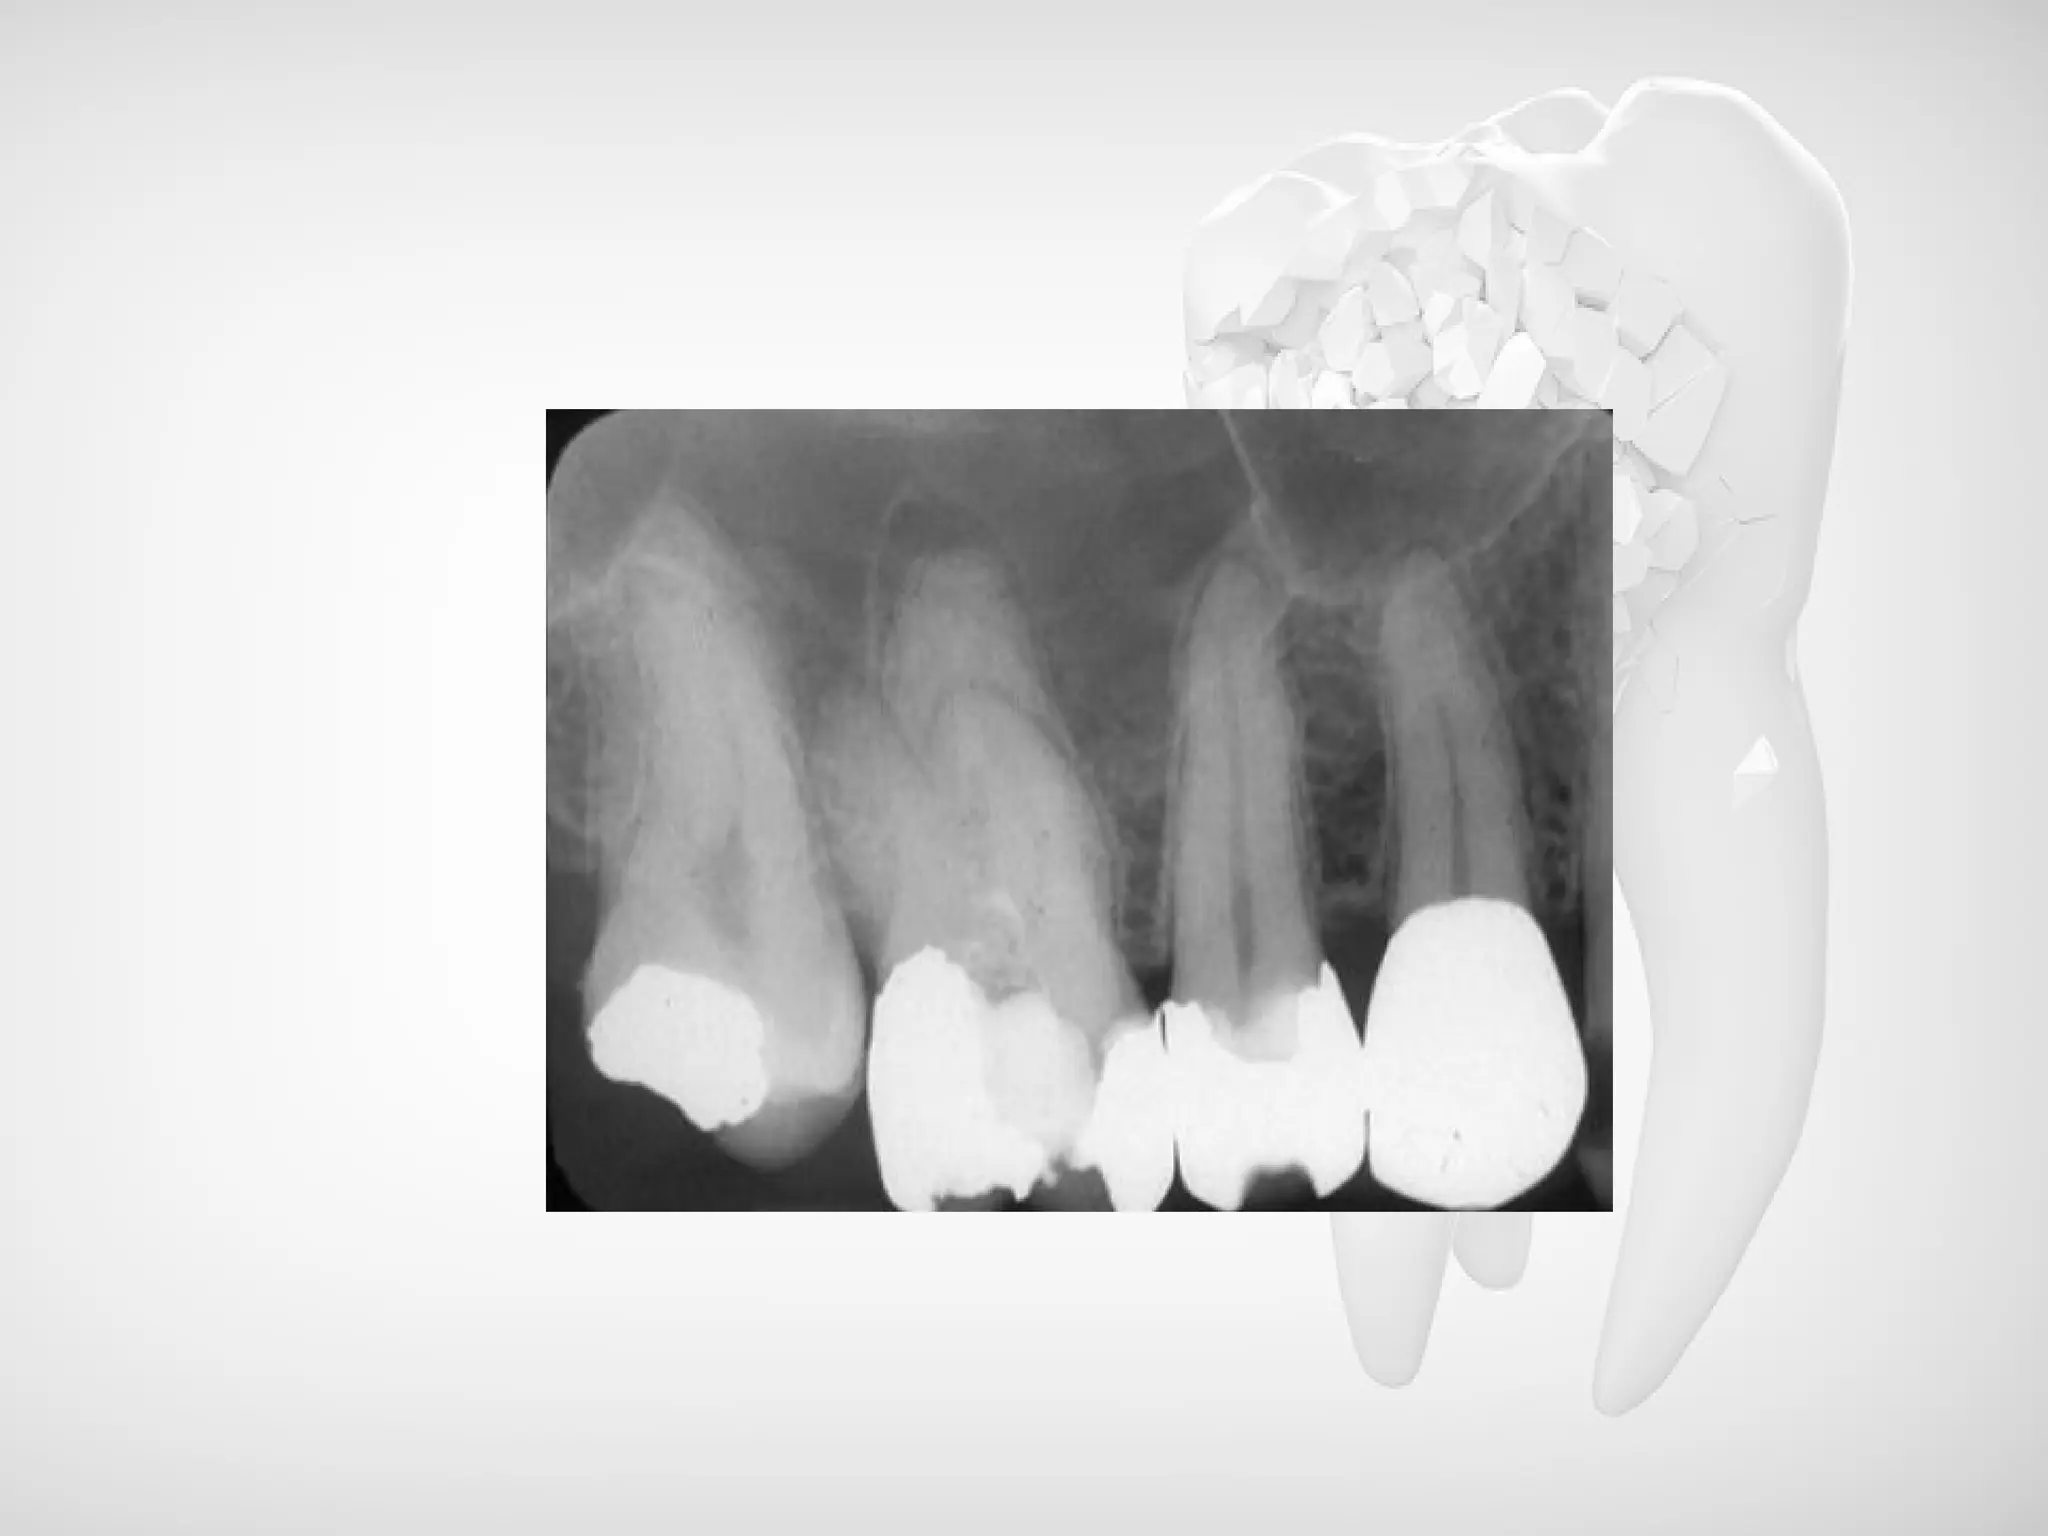

Radiographic Features:

• The acute periapical abscess is such a rapidly

progressive lesion that, except for slight thickening of

the periodontal ligament space, there is usually no

radiographic evidence of its presence.

• The chronic abscess, developing in a periapical

granuloma, presents the radiolucent area at the apex of

the tooth described previously or the radiolucency may

be ill-defined.